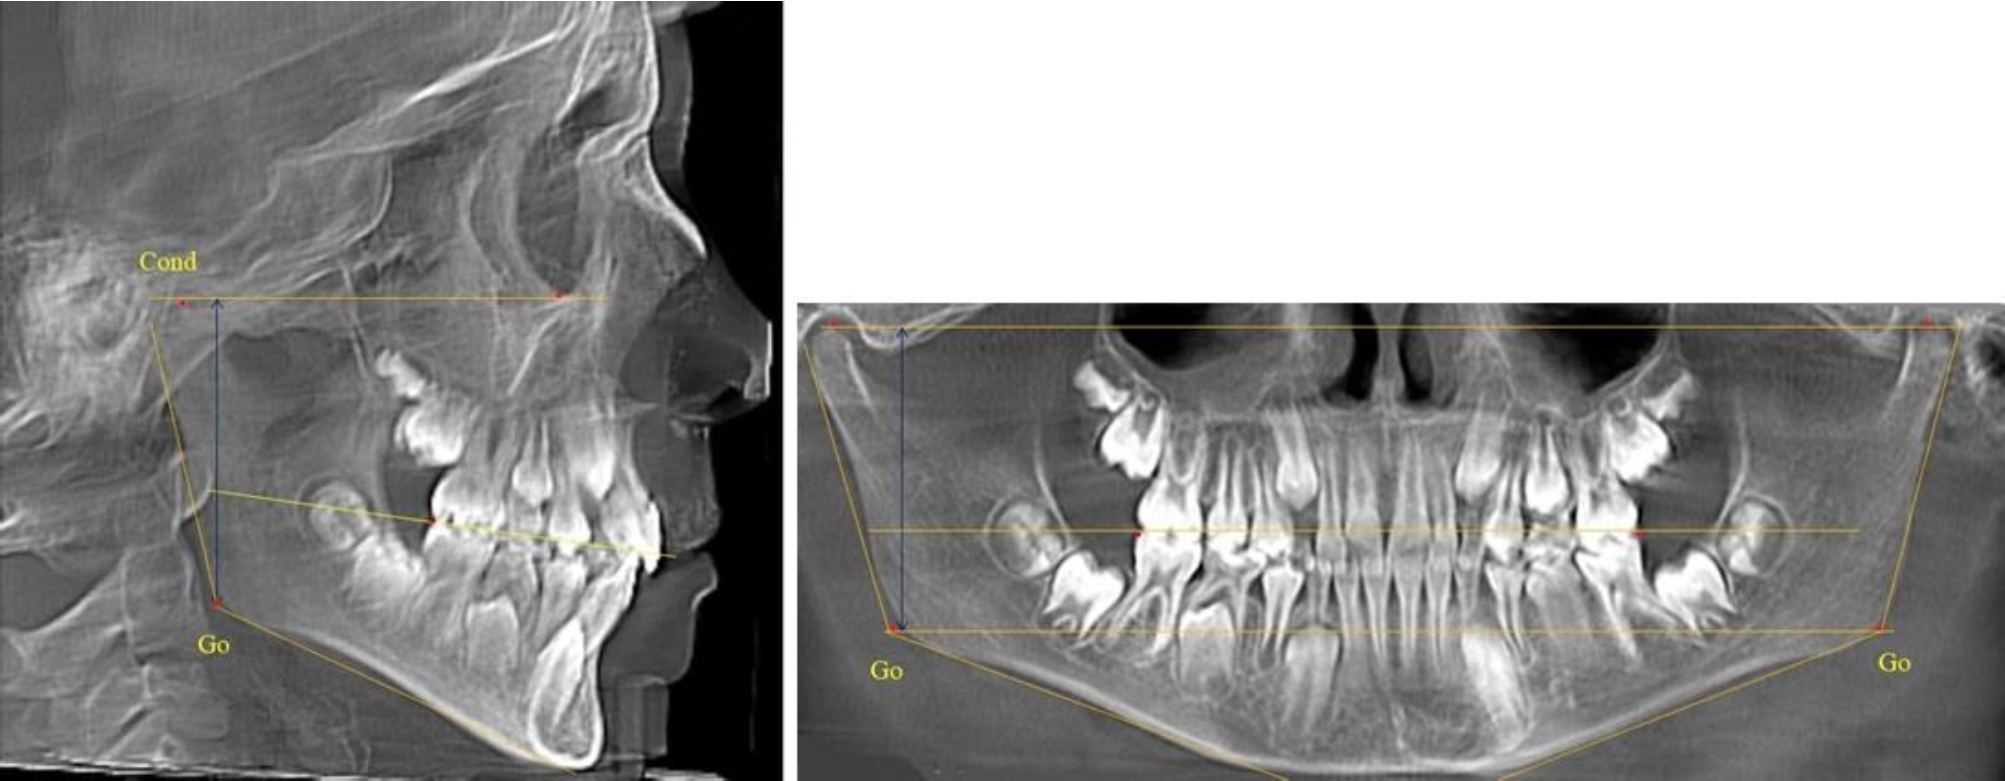

В 5-й группе были проанализированы 14 комплектов рентгенограмм, что составило (13,21 ± 3,29) % от общего числа. На всех рентгенограммах отмечен очередной этап подъема высоты прикуса, обусловленный прорезыванием вторых постоянных моляров. Окклюзионная линия делила ветвь на два отдела (рис. 5).

Рис. 5. ТРГ и ОПТГ пациента после смены молочных зубов и прорезывания вторых постоянных моляров

Высота ветви у детей 5-й группы составляла (62,87 ± 3,62) мм, что было достоверно больше, чем у детей других групп (р ˂ 0,05). При этом высота верхней окклюзионно-суставной части была (40,23 ± 2,01) мм, а нижней – (22,64 ± 1,78) мм. Высота верхней части была вдвое больше нижней, что и определяло особенности соразмерности частей ветви нижней челюсти в анализируемый возрастной период.

Относительные показатели соразмерности частей ветви нижней челюсти показали, что отношение высоты верхней части ветви к нижней в среднем составляло 1,78 ± 0,18. Отношение общей высоты ветви к верхней ее части составляло 1,56 ± 0,12, а отношение общей высоты ветви к нижней ее части было 2,78 ± 0,14, что и определяло особенности соразмерности частей ветви нижней челюсти в анализируемый возрастной период.

Таким образом, прорезывание постоянных зубов и смена молочных зубов постоянными изменяло не только высоту ветви нижней челюсти, но и изменяло соотношение ее частей, разделенных условной линией, являющейся продолжением окклюзионной линии рентгенограммы. Наиболее вариабельной структурой ветви являлась верхняя ее часть с суставным отростком. Окклюзионно-альвеолярная часть коррелировала с высотой зубочелюстных сегментов нижней челюсти.